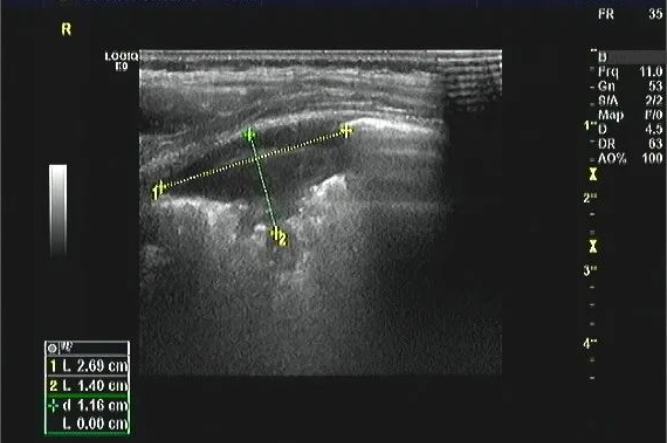

病例一:患兒1歲,發(fā)熱、咳嗽3天,左下肺部分實(shí)變區(qū),提示肺炎。